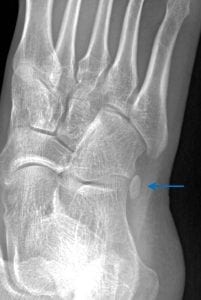

1. What is the diagnosis for the image below?